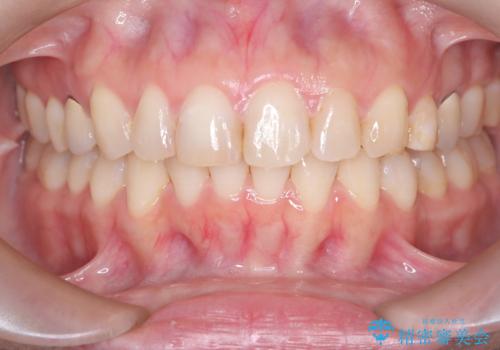

- 下の前歯のデコボコ(叢生)を気にされてご来院されました。精密な検査の結果、下の前歯を並べるスペースが不足していることが判明。患者様のご希望から、透明で目立ちにくい**インビザライン(マウスピース矯正)による治療計画を立案しました。主に歯の側面をわずかに削るIPR(歯間乳頭保護下ストリッピング)**などでスペースを確保し、下の前歯の叢生を解消することを目指します。

今回の矯正治療では、透明なマウスピース型の装置インビザラインを使用しました。目立たず、取り外しが可能なため、日常生活にほとんど影響なく治療を進めることができました。治療は、緻密に計算された計画に基づき、IPRなどで必要なスペースを確保しながら、下の前歯をスムーズに移動。これにより、長年の悩みであった下の前歯のデコボコが解消され、清掃しやすい、整った歯並びを獲得していただけました。